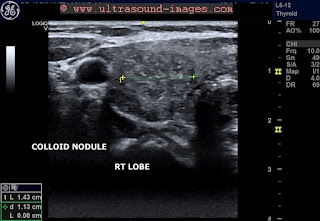

Bilateral colloid nodules in the thyroid- 1 in each lobe seen in panoramic view as well as

in focused imaging of each lobe. Both are solid and inhomogenous. Poor vascularity.

Non calcific. All features of a benign nature.